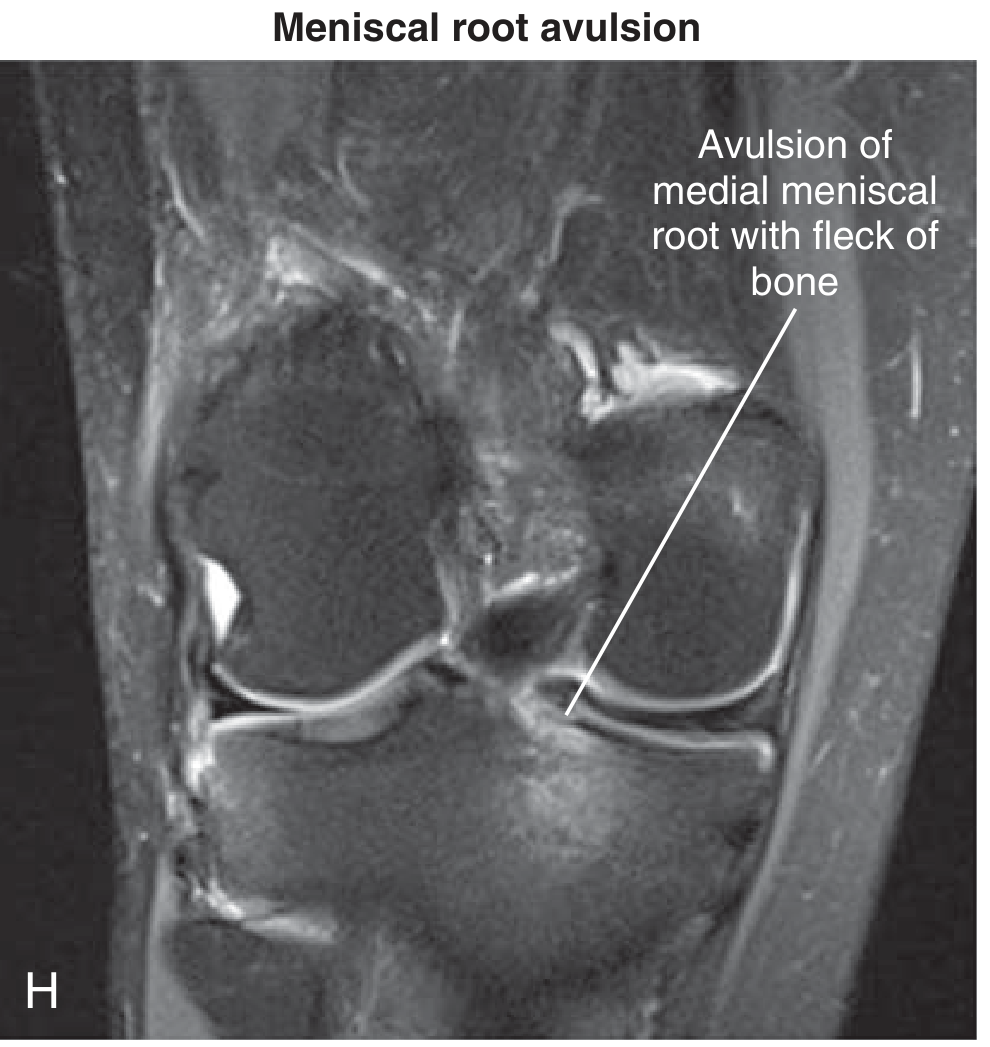

Coronal MRI — avulsion of the medial meniscal root with a fleck of bone at the tibial attachment

Meniscal root avulsion with bony fleck (Miller's Review of Orthopaedics)